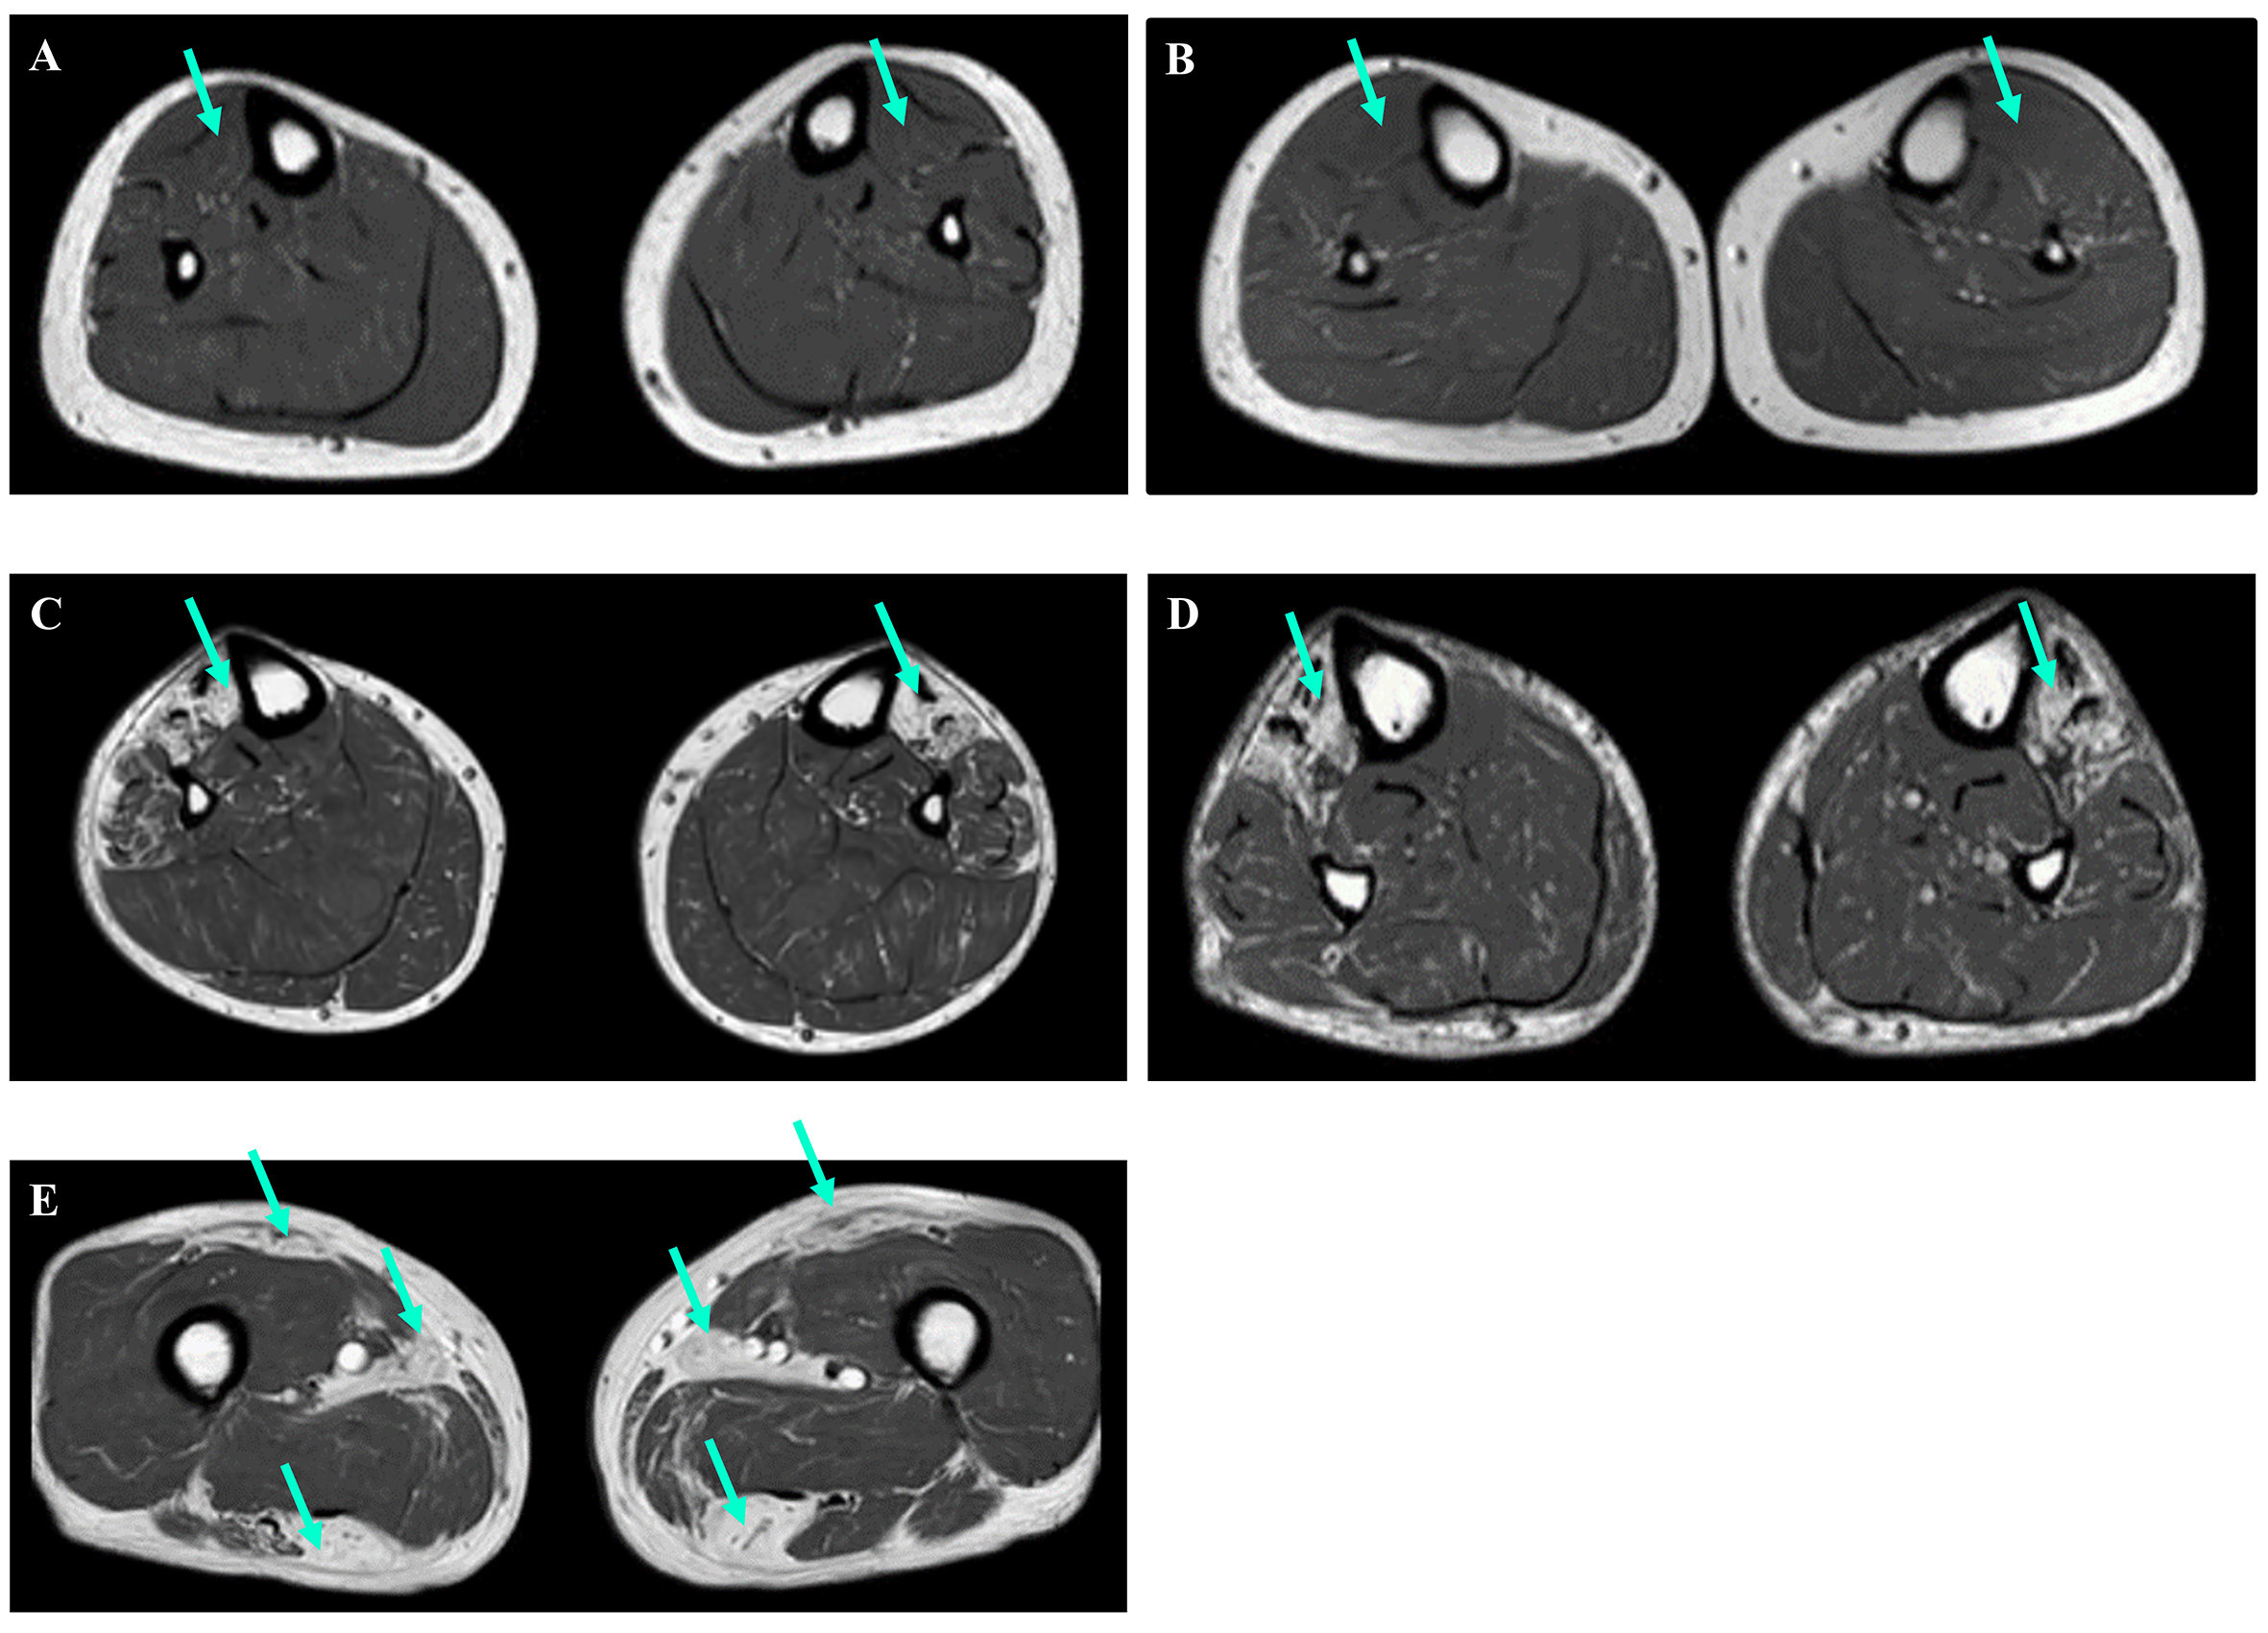

Eight FINmaj variant carriers underwent muscle MRI examinations [Figure 2, Supplementary Table 1]. Among them, three patients under the age of 50 exhibited no changes in the anterior muscles of the lower limb [Figure 2A and B]. In contrast, all patients over the age of 50 displayed signs of fatty degenerative changes. While the distribution of fatty replacement varied, a common finding was the involvement of the tibialis anterior muscle [Figure 2C and D]. Patients in the later stages of the disease, specifically those over 60 years of age, exhibited muscle atrophy and Mercuri grade IV fatty degeneration additionally in anterior and lateral distal leg muscles (extensor hallucis longus, extensor digitorum longus, and fibularis longus muscles). The same changes were also noticed in the proximal hamstring muscles (biceps femoris, semitendinosus, and semimembranosus muscles) and minor gluteal muscles [Figure 2E]. Notably, the observations were asymmetric, with one side exhibiting more fatty degeneration than the other.

Figure 2. Muscle MRI images of the lower limbs (axial T1-weighted images). (A and B) Individuals 5 and 6, both under the age of 50, showed no signs of degeneration in their tibialis anterior muscles (green arrows). (C and D) In contrast, Individuals 7 and 12, both over the age of 50, displayed changes in their tibialis anterior muscles (green arrows). (E) Additionally, MRI results for Individual 12 revealed changes in the rectus femoris, adductor longus, and hamstring muscles (green arrows).

Similar to the Finnish data, all four patients over the age of 50 years exhibited progressive weakness of the tibialis anterior muscle, difficulties with foot dorsiflexion, and fatty replacement of the distal lower limb muscles. By the age of 70 years, they also demonstrated changes in their proximal leg muscles [Figure 2C-E, Supplementary Table 1].